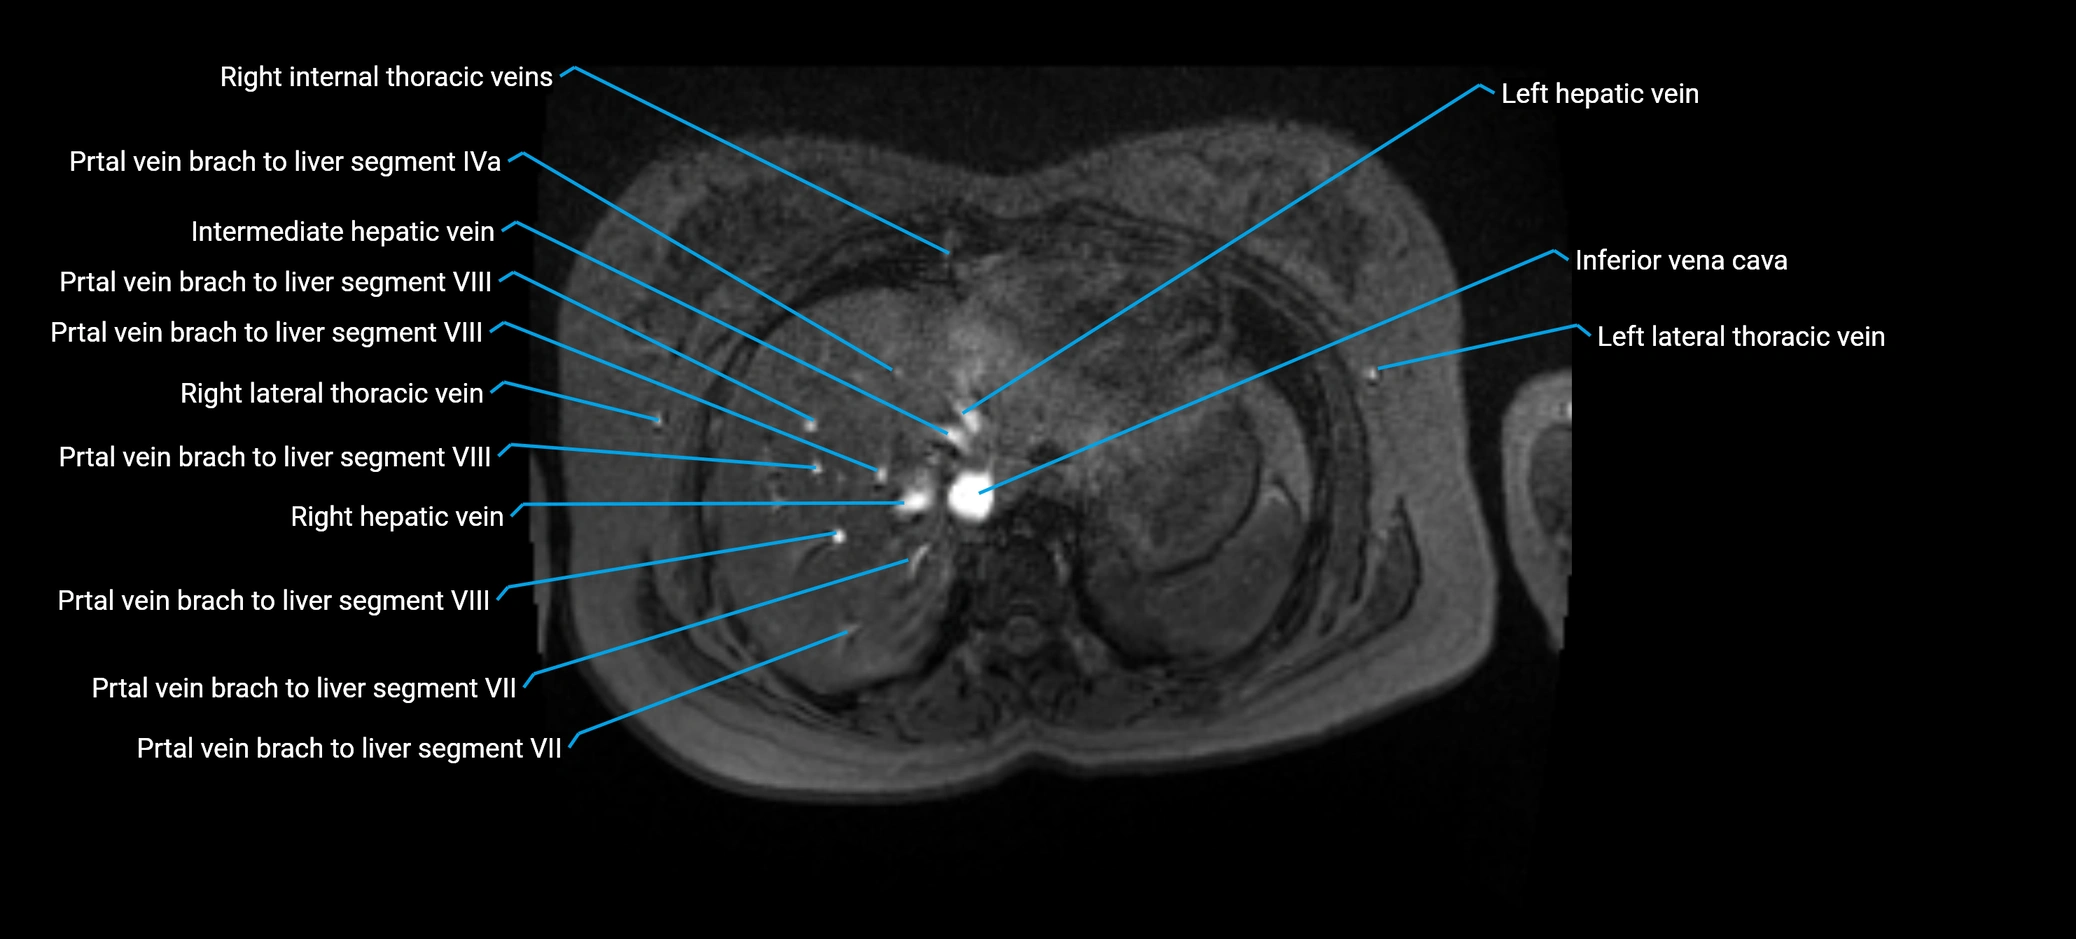

The anterior right branch of the portal vein is a major intrahepatic division of the right portal vein. After the main portal vein bifurcates into right and left branches, the right portal vein divides into anterior and posterior segmental branches.

The anterior right branch supplies the anterolateral liver segments (Segment V) and anteromedial liver segments (Segment VIII) within the right hepatic lobe. It operates as a key vascular route delivering nutrient-rich portal venous blood to the central and superior right liver.

This segmental vasculature is of major importance in hepatic surgery, embolization, segmental resection, transplantation, and imaging-based liver segmentation.

Distribution (Hepatic Segments):

• Segment V (anteroinferior right lobe)

• Segment VIII (anterosuperior right lobe)

MRV TOF (Time-of-Flight MR Venography):

• Appears as a bright, high-signal vascular channel representing flowing blood

• Clearly shows branching pattern of right portal vein into anterior and posterior branches

• Best in coronal or axial reconstructions for segmental mapping

• No need for contrast, relies on flow-related enhancement

MRI image

image